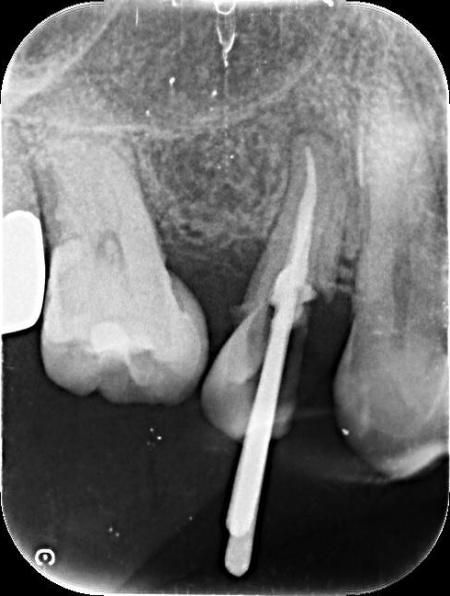

レントゲン撮影で詳しく検査した結果、虫歯が神経まで進行しており、歯根の先に黒い影が確認できます。

この影は慢性歯根膜炎と呼ばれ、虫歯による感染が神経にまで及び、歯根の先にある歯根膜という組織に炎症が起きている状態です。

このまま放置すると、炎症が広がって歯を支える骨が溶けるおそれがあるため、早急に治療をする必要があると診断しました。